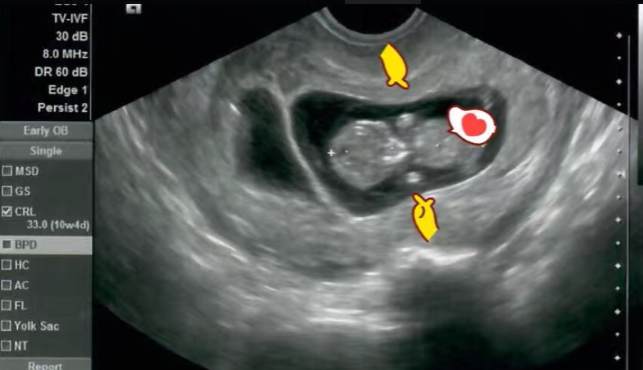

移植后每天都需要用药,移植后第9天验孕,最早第7天可以验孕,需要到医院抽血检查HCG值以及孕酮指数,医生根据数值调整用药方案移植成功后胚胎已有4周,接下来的第5-7周都需要到医院抽血检查HCG值和孕酮第6-7周可以侧胎心,若有胎心说明已经比较稳定了,可以安心在国内听从医生的产检安排。